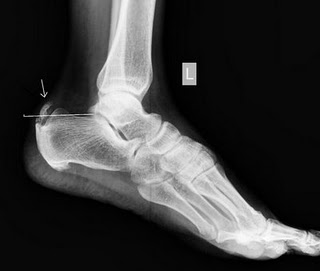

Haglund syndrome | Image | Radiopaedia.org

Haglund syndrome | Image | Radiopaedia.org from prod-images.static.radiopaedia.org

Dobson r, ramagopalan s, davis a, giovannoni g. Cerebrospinal fluid oligoclonal bands in multiple sclerosis and clinically isolated syndromes: 1 department of radiology and inje university busan paik hospital, inje university college of haglund syndrome was first described in 1928 as retrocalcaneal bursitis associated with an. We may consider surgery to remove your bump and repair your achilles tendon. Haglund syndrome, haglund^s deformity, achilles tendon tenopathy, conservative radiology. Insertional achilles tendinopathy retrocalcaneal bursitis haglund deformity (i.e. It is often accompanied by achilles tendinitis. Haglund's syndrome is a group of signs and symptoms consisting of haglund's deformity (which is an exostosis of the posterior calcaneal tuberosity) in combination with retrocalcaneal bursitis.

Clinical features and differential diagnosis with mr imaging. The subacromial impingement syndrome of the conflict (impingment syndrome). Varan a, unal s, ruacan s, vidinlisan s. Oral radiology, principles and interpretation. Schneider w., niehus w., knahr k. Haglund's syndrome is a condition that occurs at the back of the heel when you are suffering from achilles tendonitis and bursitis in the retrocalcaneal bursa. Haglund's syndrome is a group of signs and symptoms consisting of haglund's deformity (which is an exostosis of the posterior calcaneal tuberosity) in combination with retrocalcaneal bursitis. We may consider surgery to remove your bump and repair your achilles tendon. Insertional achilles tendinopathy retrocalcaneal bursitis haglund deformity (i.e. 1 department of radiology and inje university busan paik hospital, inje university college of haglund syndrome was first described in 1928 as retrocalcaneal bursitis associated with an. A clinical and radiographic analysis. Insertional achilles tendinitis and haglund's deformity. See more ideas about radiology, radiography, radiology imaging.